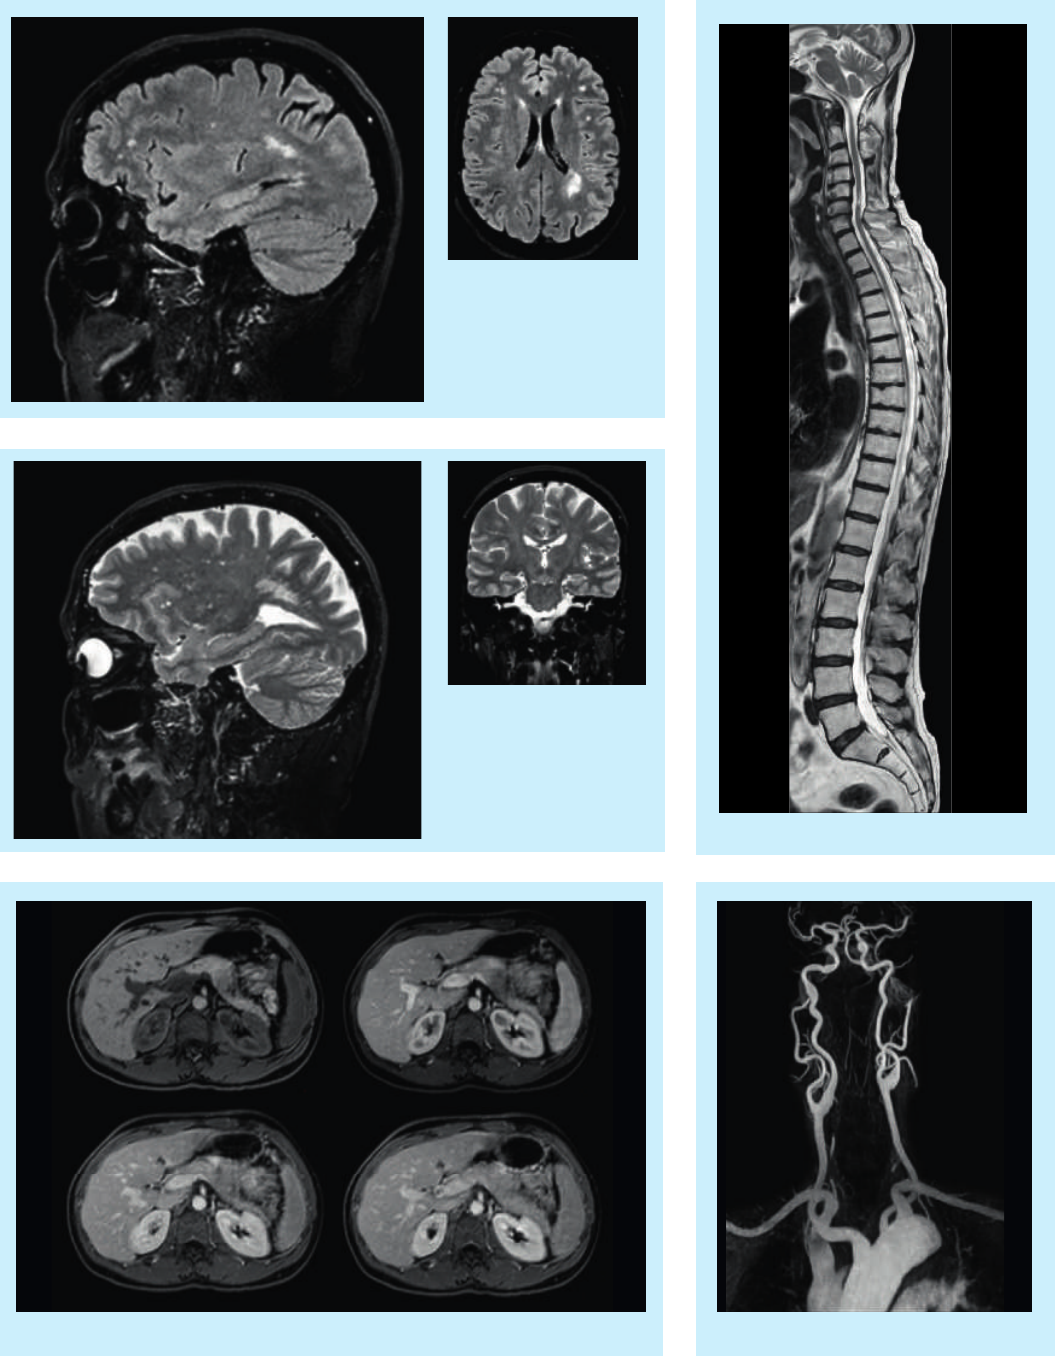

3D BrainView FLAIR.

Left: sagittal source image

Right: axial MPR

3D BrainView T2W.

Right: coronal MPR

MRA carotidsDynamic mDixon water-only of the upper abdomen

2 station T2W total spine imaging

High resolution eTHRIVE with dS-SENSE factor 9

Cine imaging of the heart

T2W imaging of both knees using dS Torso

Peripheral MRA